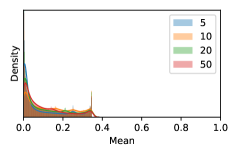

To model how different classifiers will respond to a given input , we assume that the prediction from classifier is sampled from a beta distribution that is characterized by two parameters by and . We further assume that is fixed to the same constant value for all ’s. Under this assumption, each input can be described by ( can be calculated since is fixed), easing further analysis. The Severity Level (SL) of the case represented by image can be characterized by the parameter . The larger the value of , the more severe the case of is. When and are close, the case is ambiguous as the distribution shifts towards being symmetric (i.e. signifying much disagreement among classifiers) rather than being one-sided (i.e. consensus among classifiers that is negative or positive). We provide a set of examples in Figure 2 and also Figure S.8 in the supplementary materials showing how the beta distribution can be used to capture diverse predictions given by an ensemble learner.

In contrast, the MC-dropout method showed the worst overall performance among the three, as it can be seen from the high ratios of SL0 examples among the uncertain negatives in Figure 4. The histograms in Figure 2 provides another perspective to look into the phenomenon, where a decent proportion of MC-dropout model’s predictions on SL0 inputs entailed low confidence (far from 0 or 1), which from another angle explained why MC-dropout was less specific in terms of lower FNP; many no-DR inputs (i.e. SL0) were erroneously assigned high uncertainty by MC-dropout models.

As discussed in Section 5.1 and Section 5.3 in the main paper, the mean metric and the stacking ensemble will have better performance in the precision (specificity) on the ambiguous data. Here, more detailed results are shown in Figures S.3 & S.6 and Table S.1. Figures S.3 & S.4 show the histograms of the uncertainty score for Kaggle-DR and Messidor-2 datasets that are the in-distribution (i.d.) dataset in our experiment and FigureS.5 & S.6 show the histograms for ImageNet and CIFAR-10 datasets, which is the o.o.d. datasets in our experiment. Each group of histograms contains results from the three evaluated ensemble methods (stacking ensemble, MC-dropout and TTA) and the three uncertainty metrics (mean, var and kl). Additional detailed results not displayed in Figure 4 can be found in Table S.1, which shows the proportion of the data of different SLs varies across different . For comparison, we also included in Table S.1 the results from single learners, and the proportions of data of different SLs (before any selection was made).